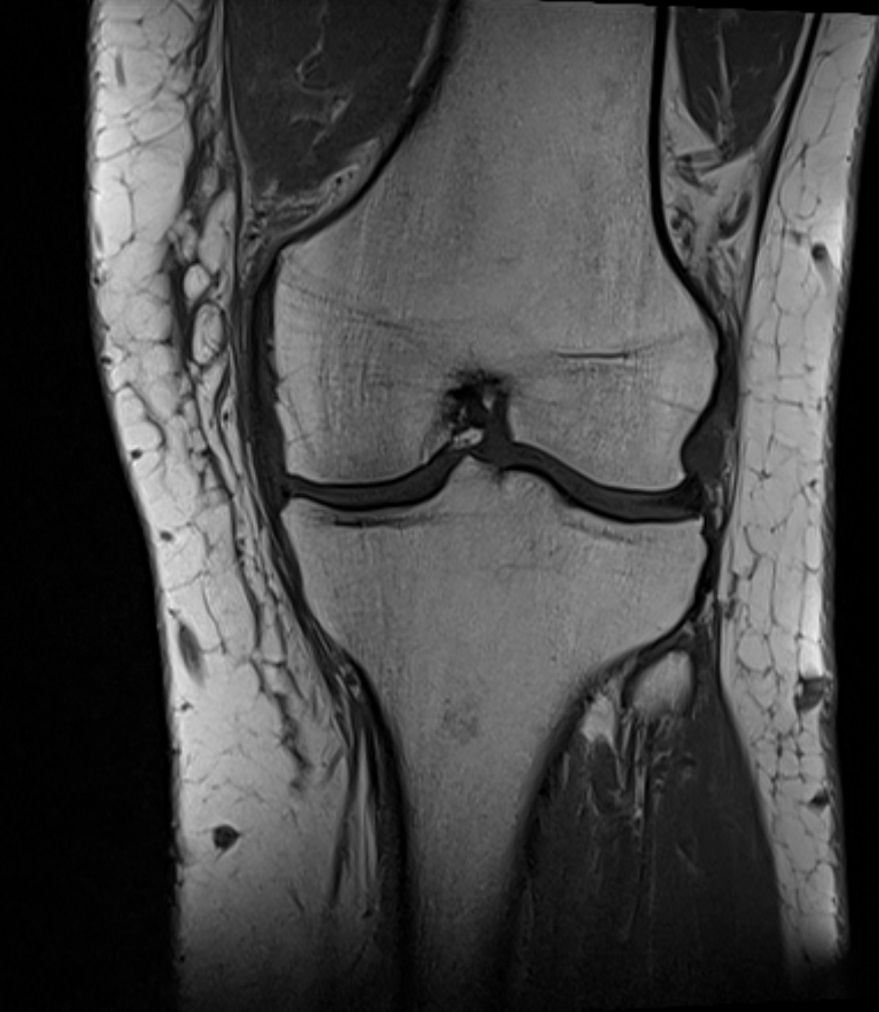

MRT Aufnahme eines Kniegelenks